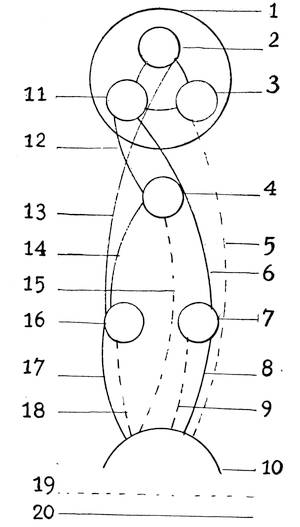

At this period a little semicircular crescentic fold attached to the dorsal margin of the aperture of the vagina arises and forms the hymen, an organ which has always played such an important rôle in the fancy of all nations.

The upper blind ends of the Müllerian ducts, with their expanded funnel-shaped mouths, diverge and form the oviducts, or the Fallopian tubes.

The ovary is produced from the asexual stage by the following metamorphosis. The mesothelial cells on the peritoneal surface of the sexual gland change into the germinal epithelium and form the so-called egg-columns or sexual cord which represent the primitive ova.

At the caudal end, the Müllerian ducts fuse together into

one, the walls, along the entire line of the union, degenerate,

and the two ducts thus form a single duct, the later vagina and

uterus. Until the fifth month there is no distinction between25

26

vagina and uterus, the two organs form a single sac-like structure.

At the beginning of the fifth month, a circular ridge in

the wall of the sac makes its appearance and marks the division

between the vagina and the uterus. When the lower portion of

the two Müllerian ducts have fused to form a single canal, the

utero-vaginal sac, the lumen of the vagina is still obliterated,

being filled with epithelial cells. By the breaking down of the

central epithelial cells, the cavity is established.